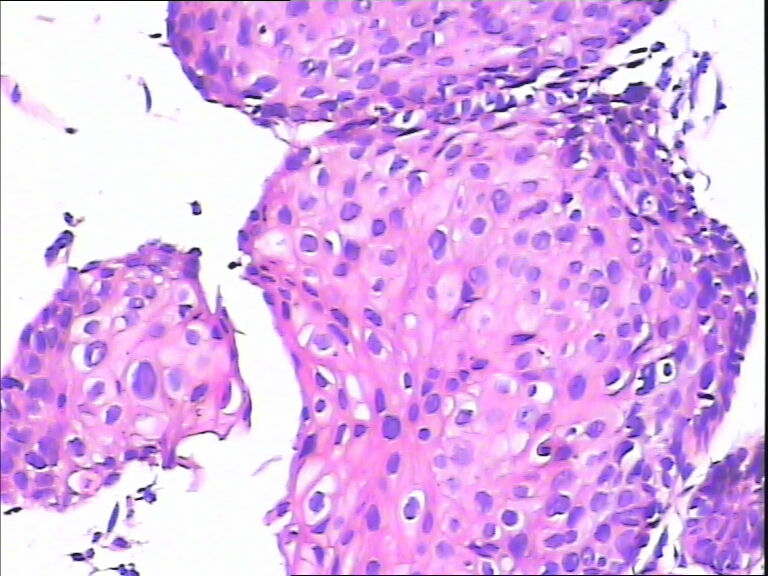

45y,触血,宫颈多点活检。